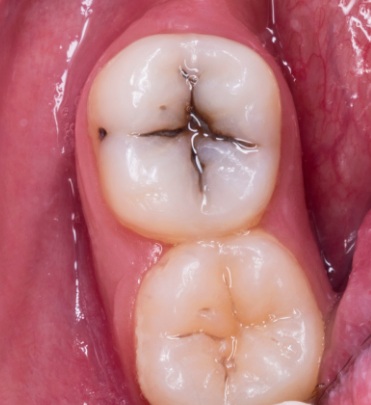

If the filling has darkened not on the outside, but as if ‘from the inside’ or along the contour, this is a serious cause for concern. Here we deal with biological processes.

- Impaired marginal fit. This is the most dangerous cause. A microgap (microleakage) forms between the material and the tooth. Bacteria and oral fluid enter the area, and secondary caries develops. The edge of the filling looks like a thin, dark, or brown line.